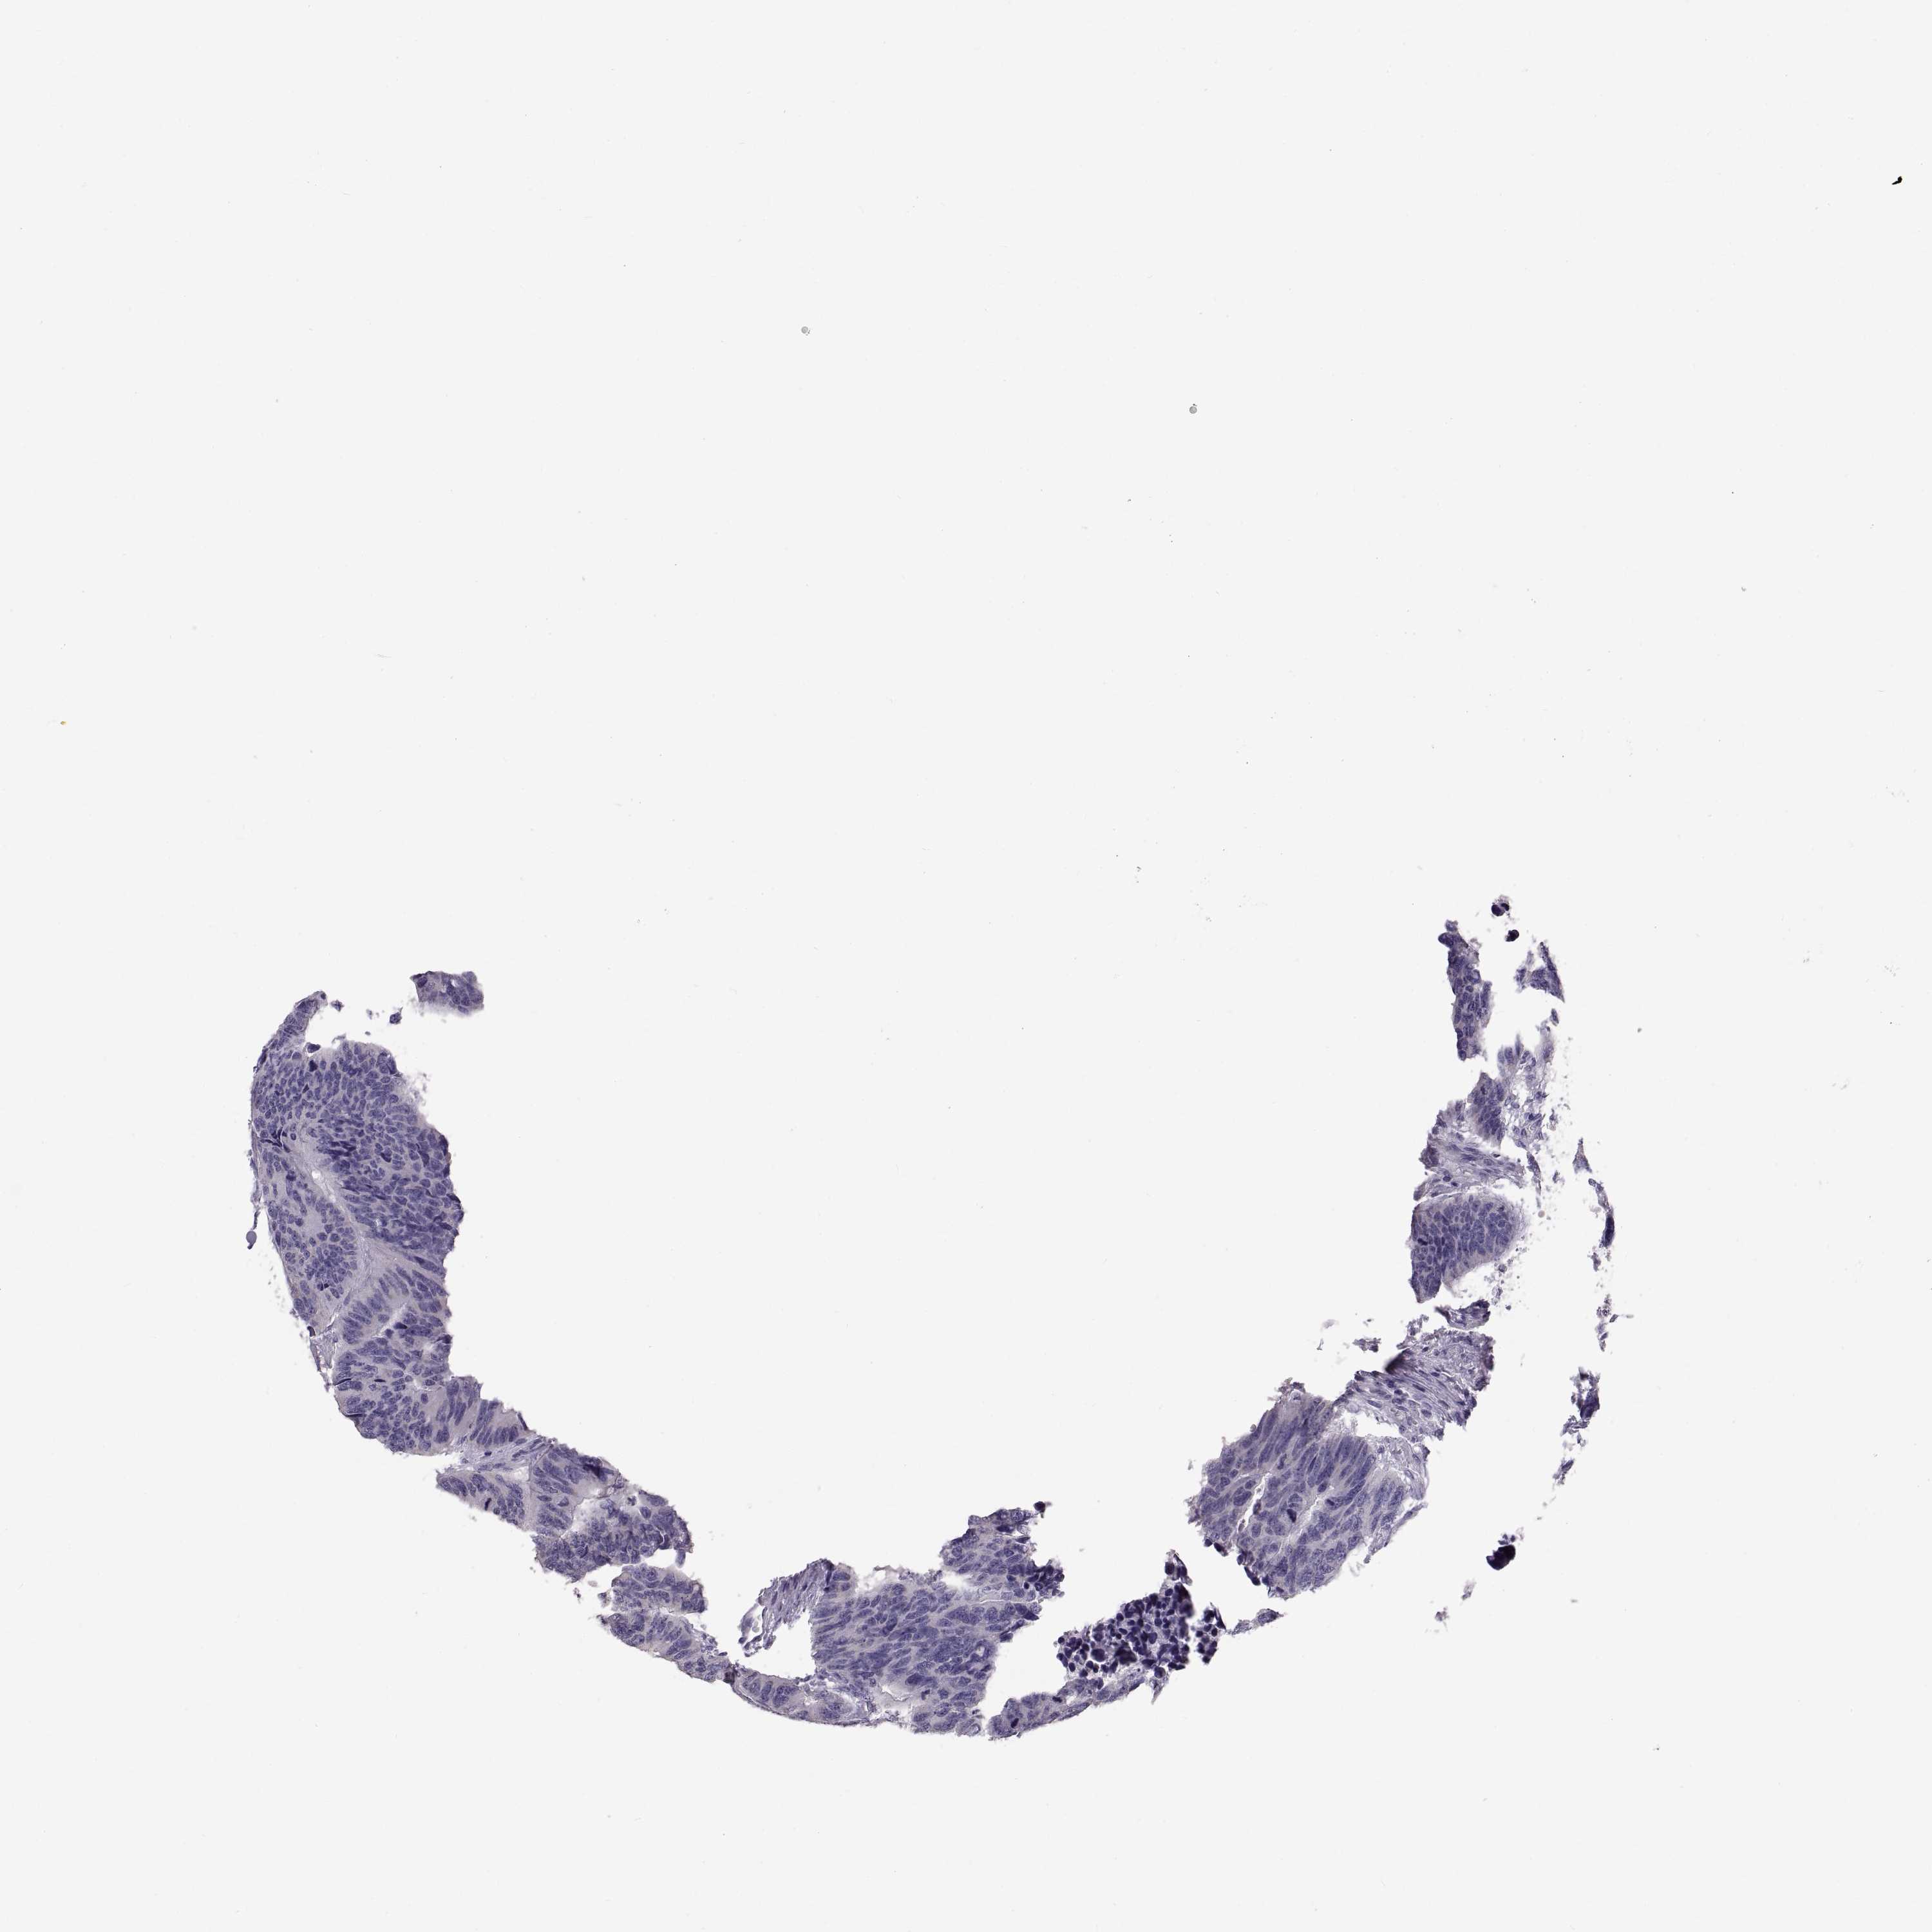

CANCER COLORECTAL CANCER Show tissue menu

Colorectal cancer

Colon adenocarcinoma